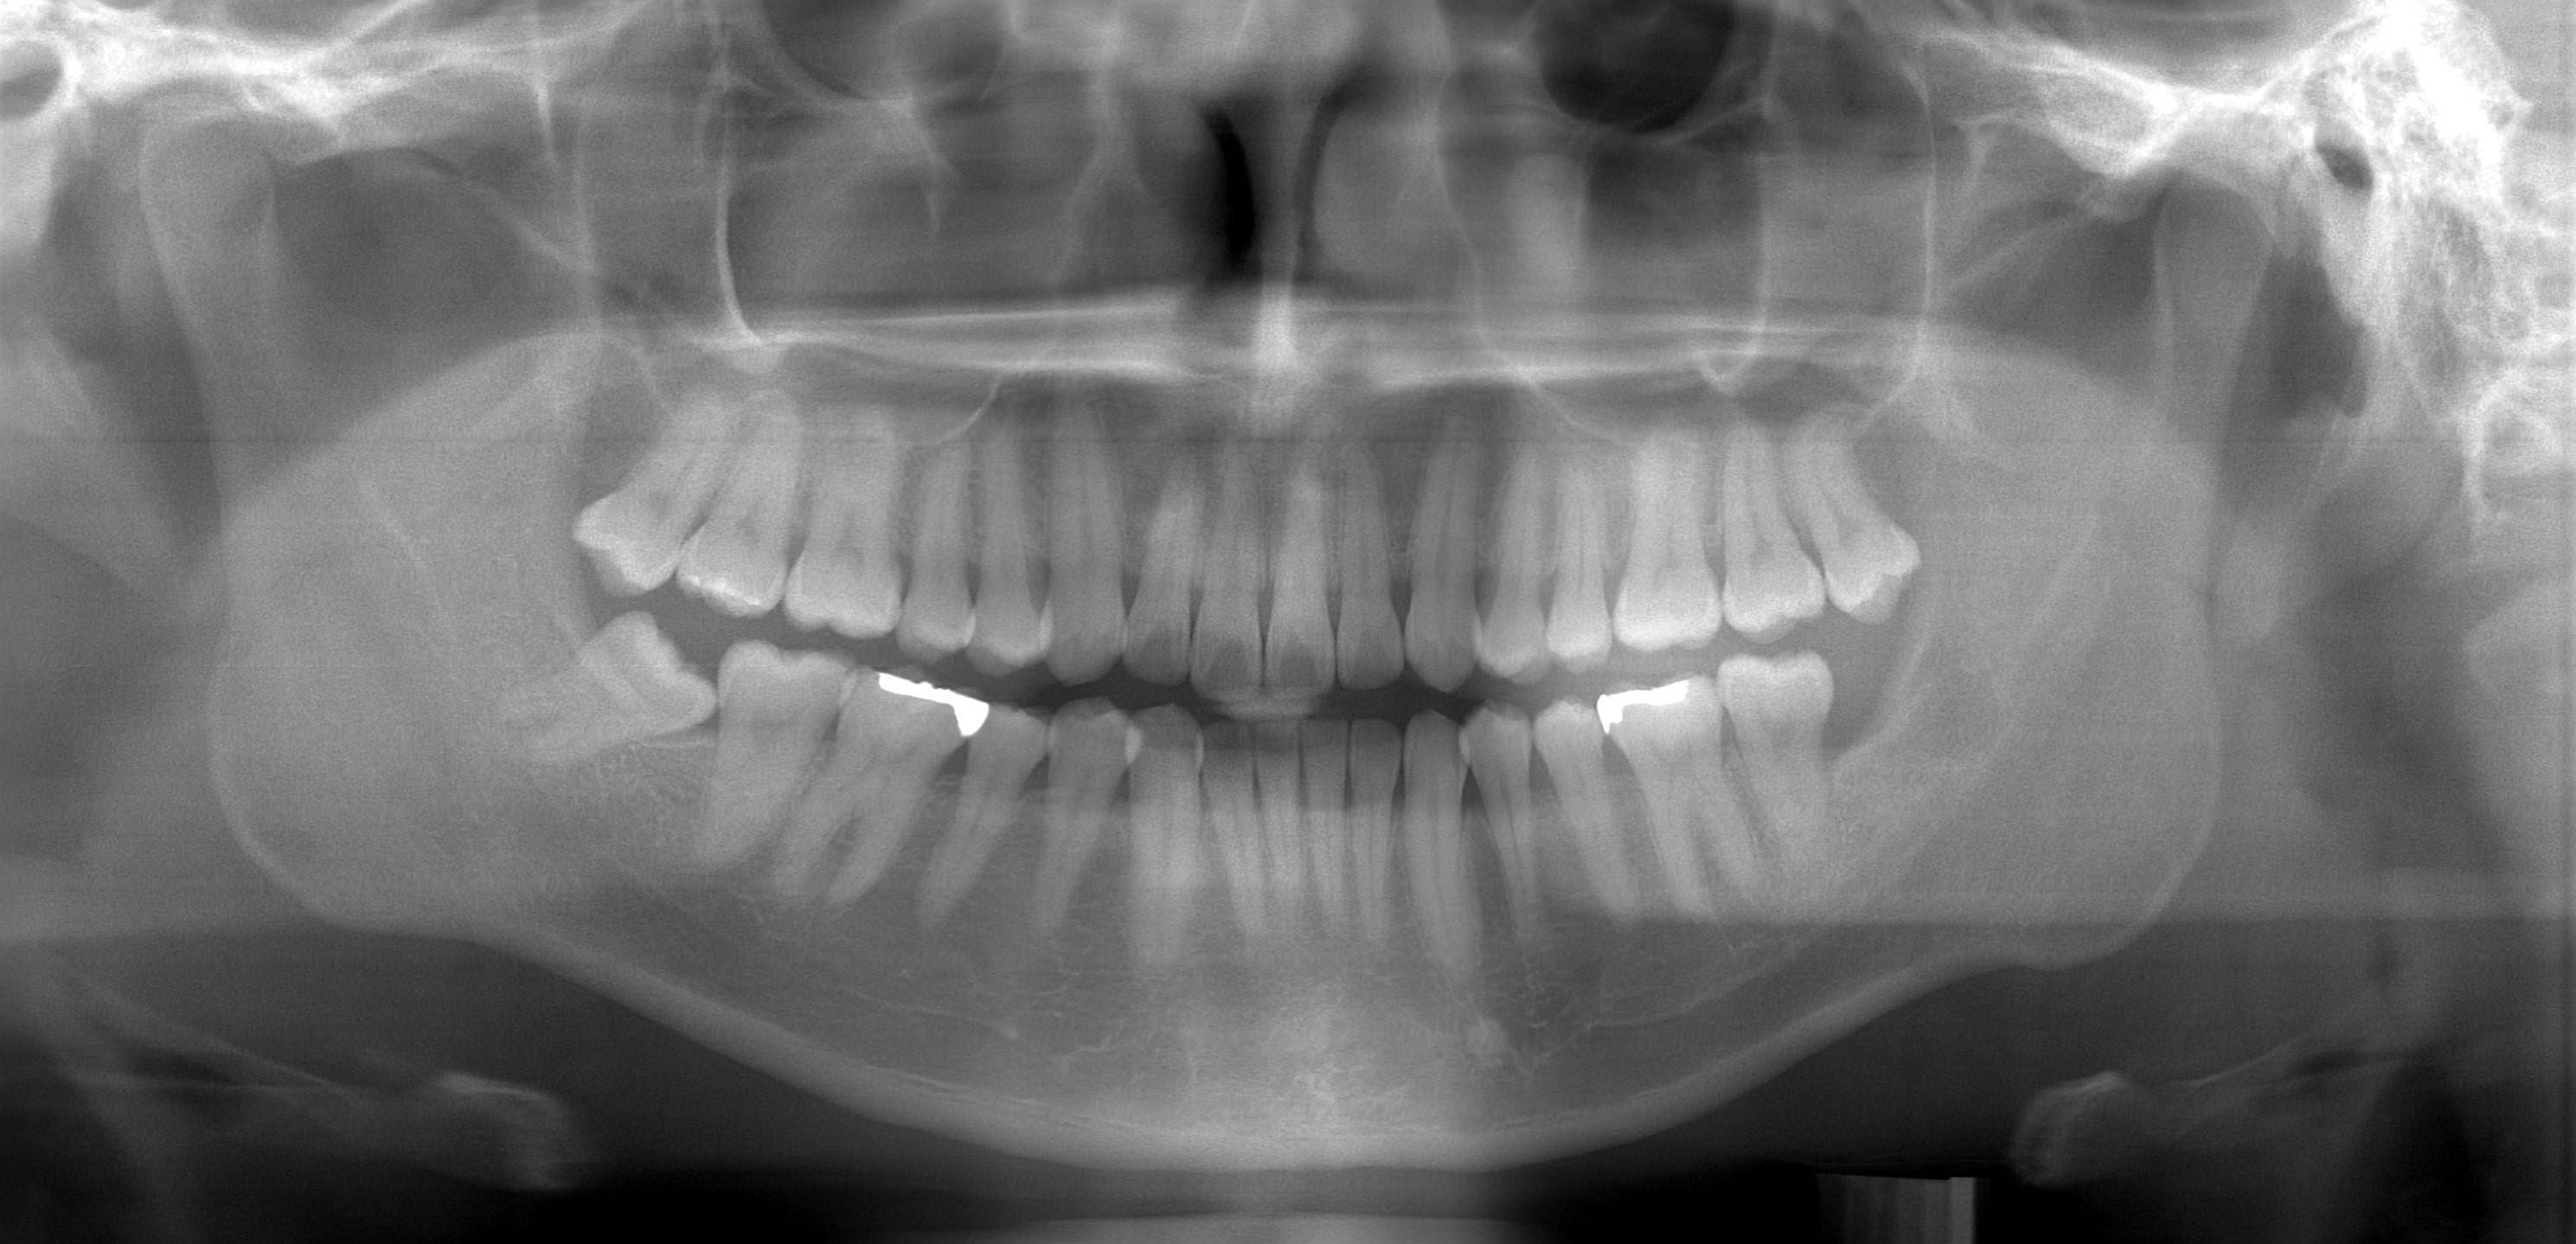

精密検査・診断

精密検査

費用:22,000円

• レントゲン撮影(パノラマ・セファロ)

• 口腔内・顔貌写真撮影

• 歯型採得・模型作製

• 咬合・顎機能検査

🔍 詳細な検査で最適な治療計画を立案